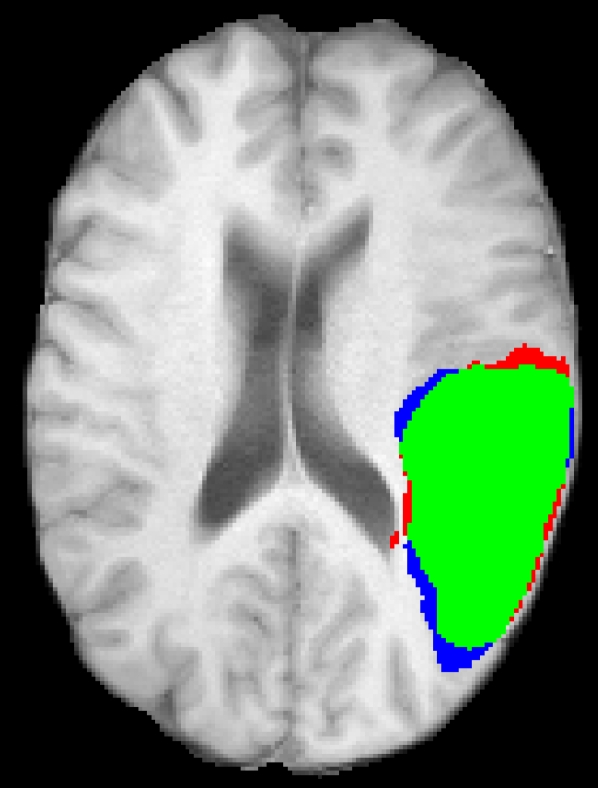

Representative examples of the qualitative results from the proposed method can be found in Figure 4. Cases 9 and 15 represent the overall results of the proposed methodology, correctly detecting the lesions in most cases with an outline that approximates the provided gold standard. Among the observed limitations are inaccurate borders and over/under segmentation of certain regions. For instance, in case 5 the lesion was undersegmented due to a heterogeneous appearance of the gold standard lesion while in case 13 two false positive lesions are detected due to the previous existence of chronic stroke lesions with a similar appearance.

Figure 4: Output segmentation masks of representative cases from the training images of ISLES 2015 SISS dataset. On all images, true positives are denoted in green, false positives in red and false negatives in blue.